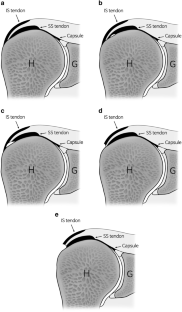

Fig. 2